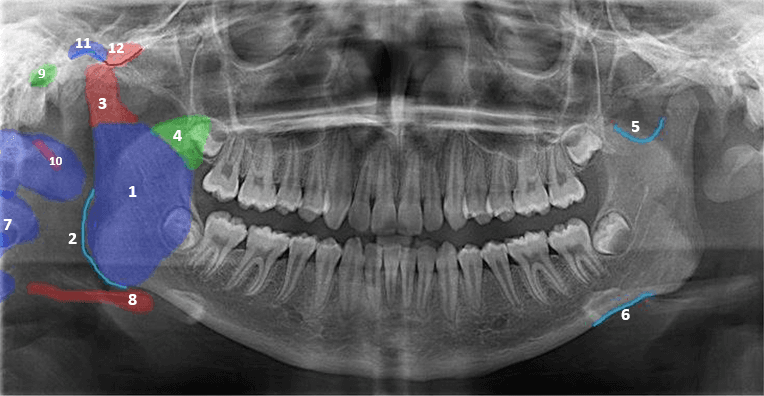

Mark areas on the teeth as calcified, on each tooth. Visually present the radiograph findings using a color scale for better decision-making and collaboration, making it easier to prioritize and visualize patient information.